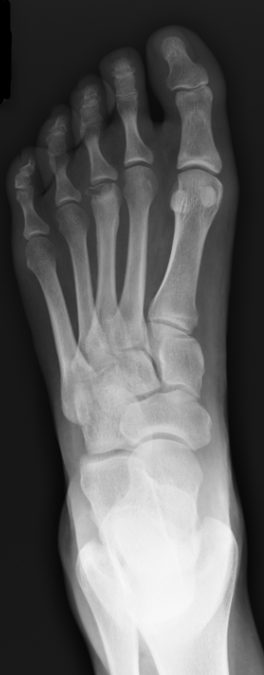

What’s the Diagnosis? Gepost op 25 juni 201825 juni 2018 door netwerkvsseh What’s the Diagnosis? @emdaily.cooperhealth.org Dit delen: Delen op X (Opent in een nieuw venster) X Share op Facebook (Opent in een nieuw venster) Facebook Delen op LinkedIn (Opent in een nieuw venster) LinkedIn E-mail een link naar een vriend (Opent in een nieuw venster) E-mail Afdrukken (Opent in een nieuw venster) Print Vind-ik-leuk Aan het laden... Gerelateerd